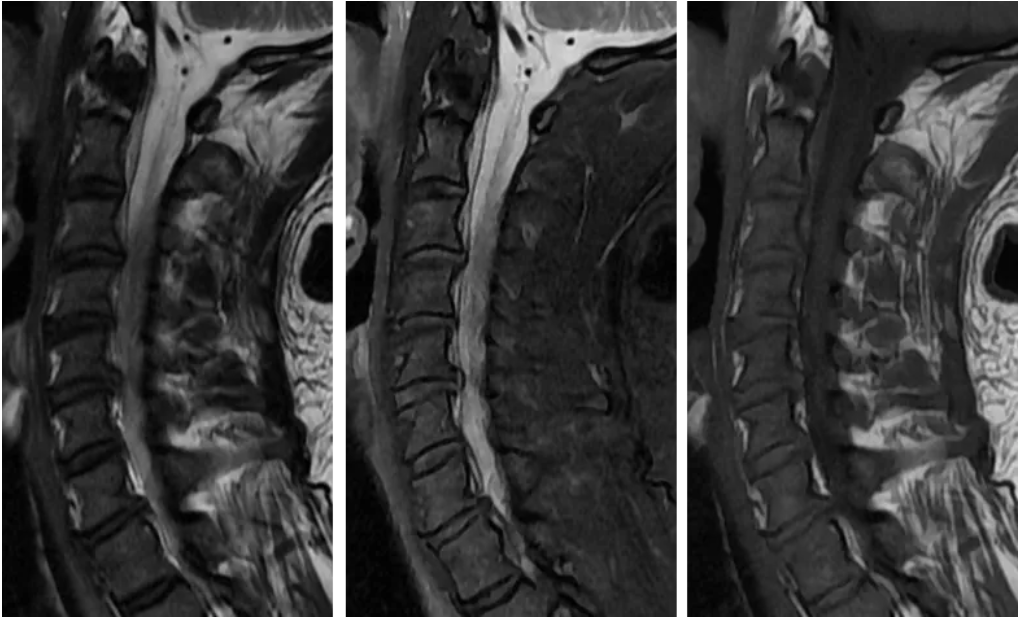

重建效果图:

五、综合诊断 脊髓亚急性联合变性(SCD) v由于维生素B12的摄入、吸收、结合、转运或代谢障碍导致体内含量不足而引起的中枢和周围神经系统变性的疾病。 v主要累及脊髓后索、侧索及周围神经,影像表现为倒置的“V”。 追问病史,该患者有长期大量饮酒史,胃功能受损